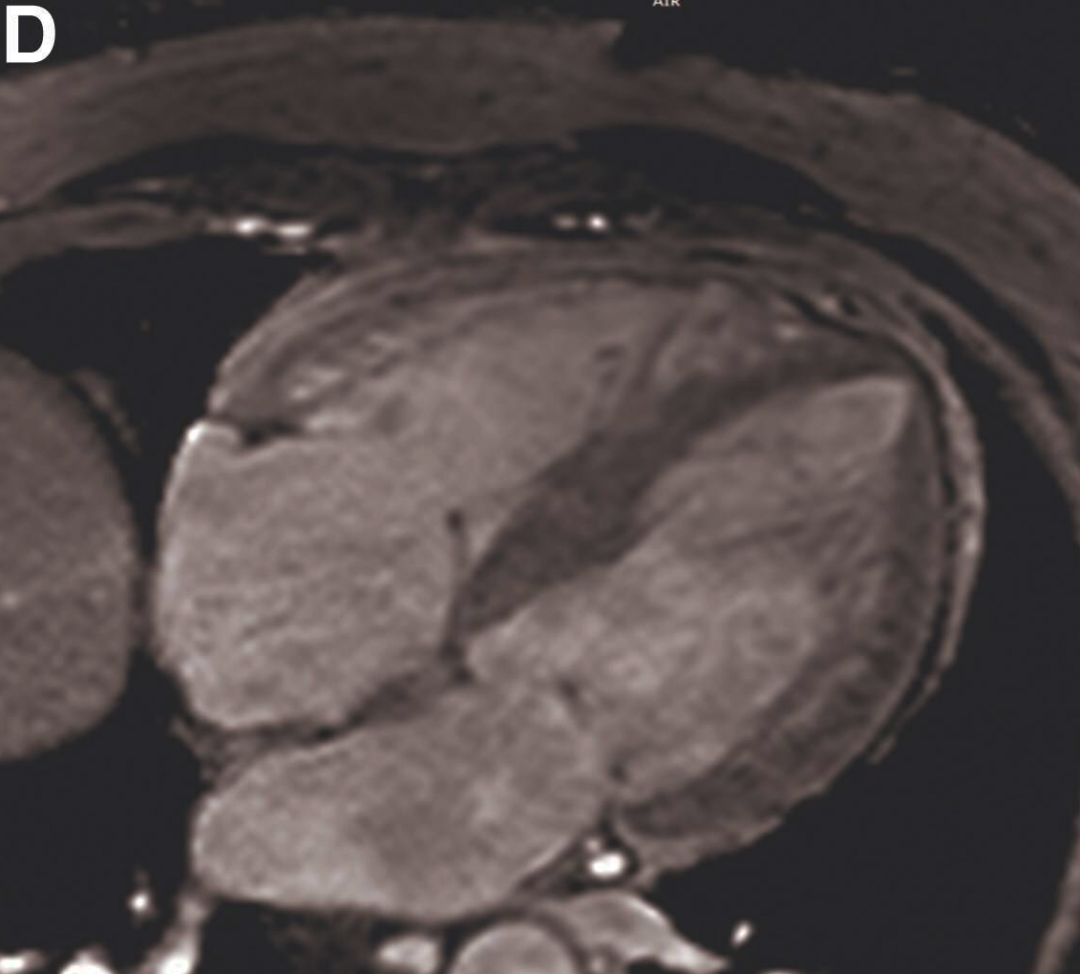

为进一步明确病变特征并排除其他潜在心肌疾病及晚期钆增强(LGE),行CMR检查,结果显示心尖部外侧壁小梁密集增厚(图 C,视频3)。呈结节状,且相互融合,看似“假性肿物”。

图C 心脏磁共振成像(心尖四腔心切面)显示左心室心尖段小梁呈簇状和结节状

视频3